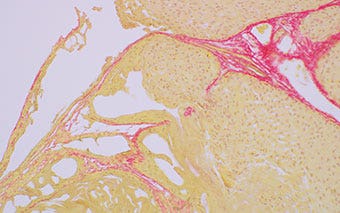

쥐의 폐 조직(피크로시리우스 빨간색으로 착색됨)

명시야 관찰

그림 1: 100W 할로겐 램프

그림 2: 고광도 및 하이 컬러 렌더링 LED가 장착된 BX53 현미경